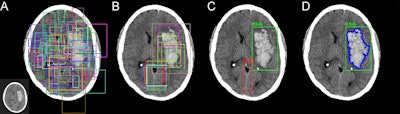

Next, 3D voxel-level mask annotations were manually created for all of the cases with hemorrhage, and the data were fed into a mask-based residual 3D/2D CNN architecture for training to predict hemorrhage, Chang said.

After fivefold cross-validation, the CNN yielded a high level of performance for detecting hemorrhage on the 10,159 exams. The algorithm missed only 26 (2.9%) of the 901 hemorrhages in the study, with similar performance across all sizes and types.

The mask residual CNN component of the deep-learning architecture can generate volume calculations of the hemorrhages that correlate highly with ground-truth measurements, according to Chang.